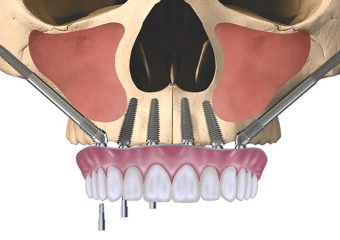

Zygomatic Implants یا ایمپلنت زیگوماتیک یکی از روش های ایمپلنت دندان در اواخر ۱۹۸۰ مورد استفاده قرار گرفته است. ایمپلنت زیگوماتیک به نام زایگوما نیز شناخته می شود. این روش در شرایطی کاربرد دارد که استخوان فک فوقانی به شدت ازبین رفته و امکان کاشت ایمپلنت در آن وجو ندارد. در ایمپلنت زایگوما پیوند استخوان انجام نمی شود و پایه ایمپلنت در استخوان زیگوماتیک یا همان استخوان گونه کاشته می شود. از این رو به آن ایمپلنت زیگوماتیک گفته می شود. در ادامه این مقاله سایت دکتر ندا مکانیک متخصص ایمپلنت اصفهان به مطالعه و بررسی کاربردهای ایمپلنت دندان زیگوماتیک خواهیم پرداخت.

پایه ایمپلنت در روش زایگوما از استخوان ضعیف فک و مجاورت سینوس ها عبور کرده و پایه ایمپلنت زیر استخوان گونه (زیگوماتیک) قرارمی گیرند یعنی استخوان گونه پشتیبان ونگه دارنده ی پایه ایمپلنت است.

در ایمپلنت دندان به روش سنتی، پایه های ایمپلنت در استخوانی به نام زیگولا تعبیه می شوند. که اگر این استخوان تراکم لازم را دارا نباشد بنابراین یکی از راه حل ها، کاشت پایه در استخوان زیگوماتیک (استخوان گونه) که به مراتب تراکم استخوان در این ناحیه بیشتر است، می باشد. ایمپلنت زیگوماتیک نیازمند کاشت دوپایه زیگوماتیک و ۴ عدد پایه ایمپلنت سنتی است. اما در مواردی که استخوان دندان های پیشین و قدامی خیلی تحلیل رفته باشد می توان از ۴ عدد ایمپلنت زیگوماتیک استفاده کرد. در ایمپلنت زیگوماتیک از روش بریج هم استفاده می شود. ایمپلنت های دندانی زیگوماتیک ۳ تا ۵.۵۲ میلی متری هستند که پروتز ها هم با زاویه ۴۵ درجه قرار می گیرند.